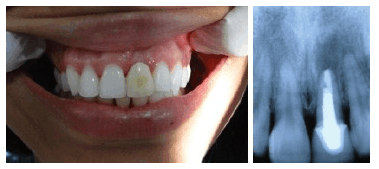

Para os pacientes que possuem boa quantidade óssea, atualmente já é possível a realização de Implante Imediato. Nestes casos o implante é colocado, e a prótese provisória pode ser instalada imediatamente ou em até 3 dias.

Nos casos onde o osso está extremamente atrofiado, ou com pouca quantidade, lança-se mão dos enxertos ósseos.